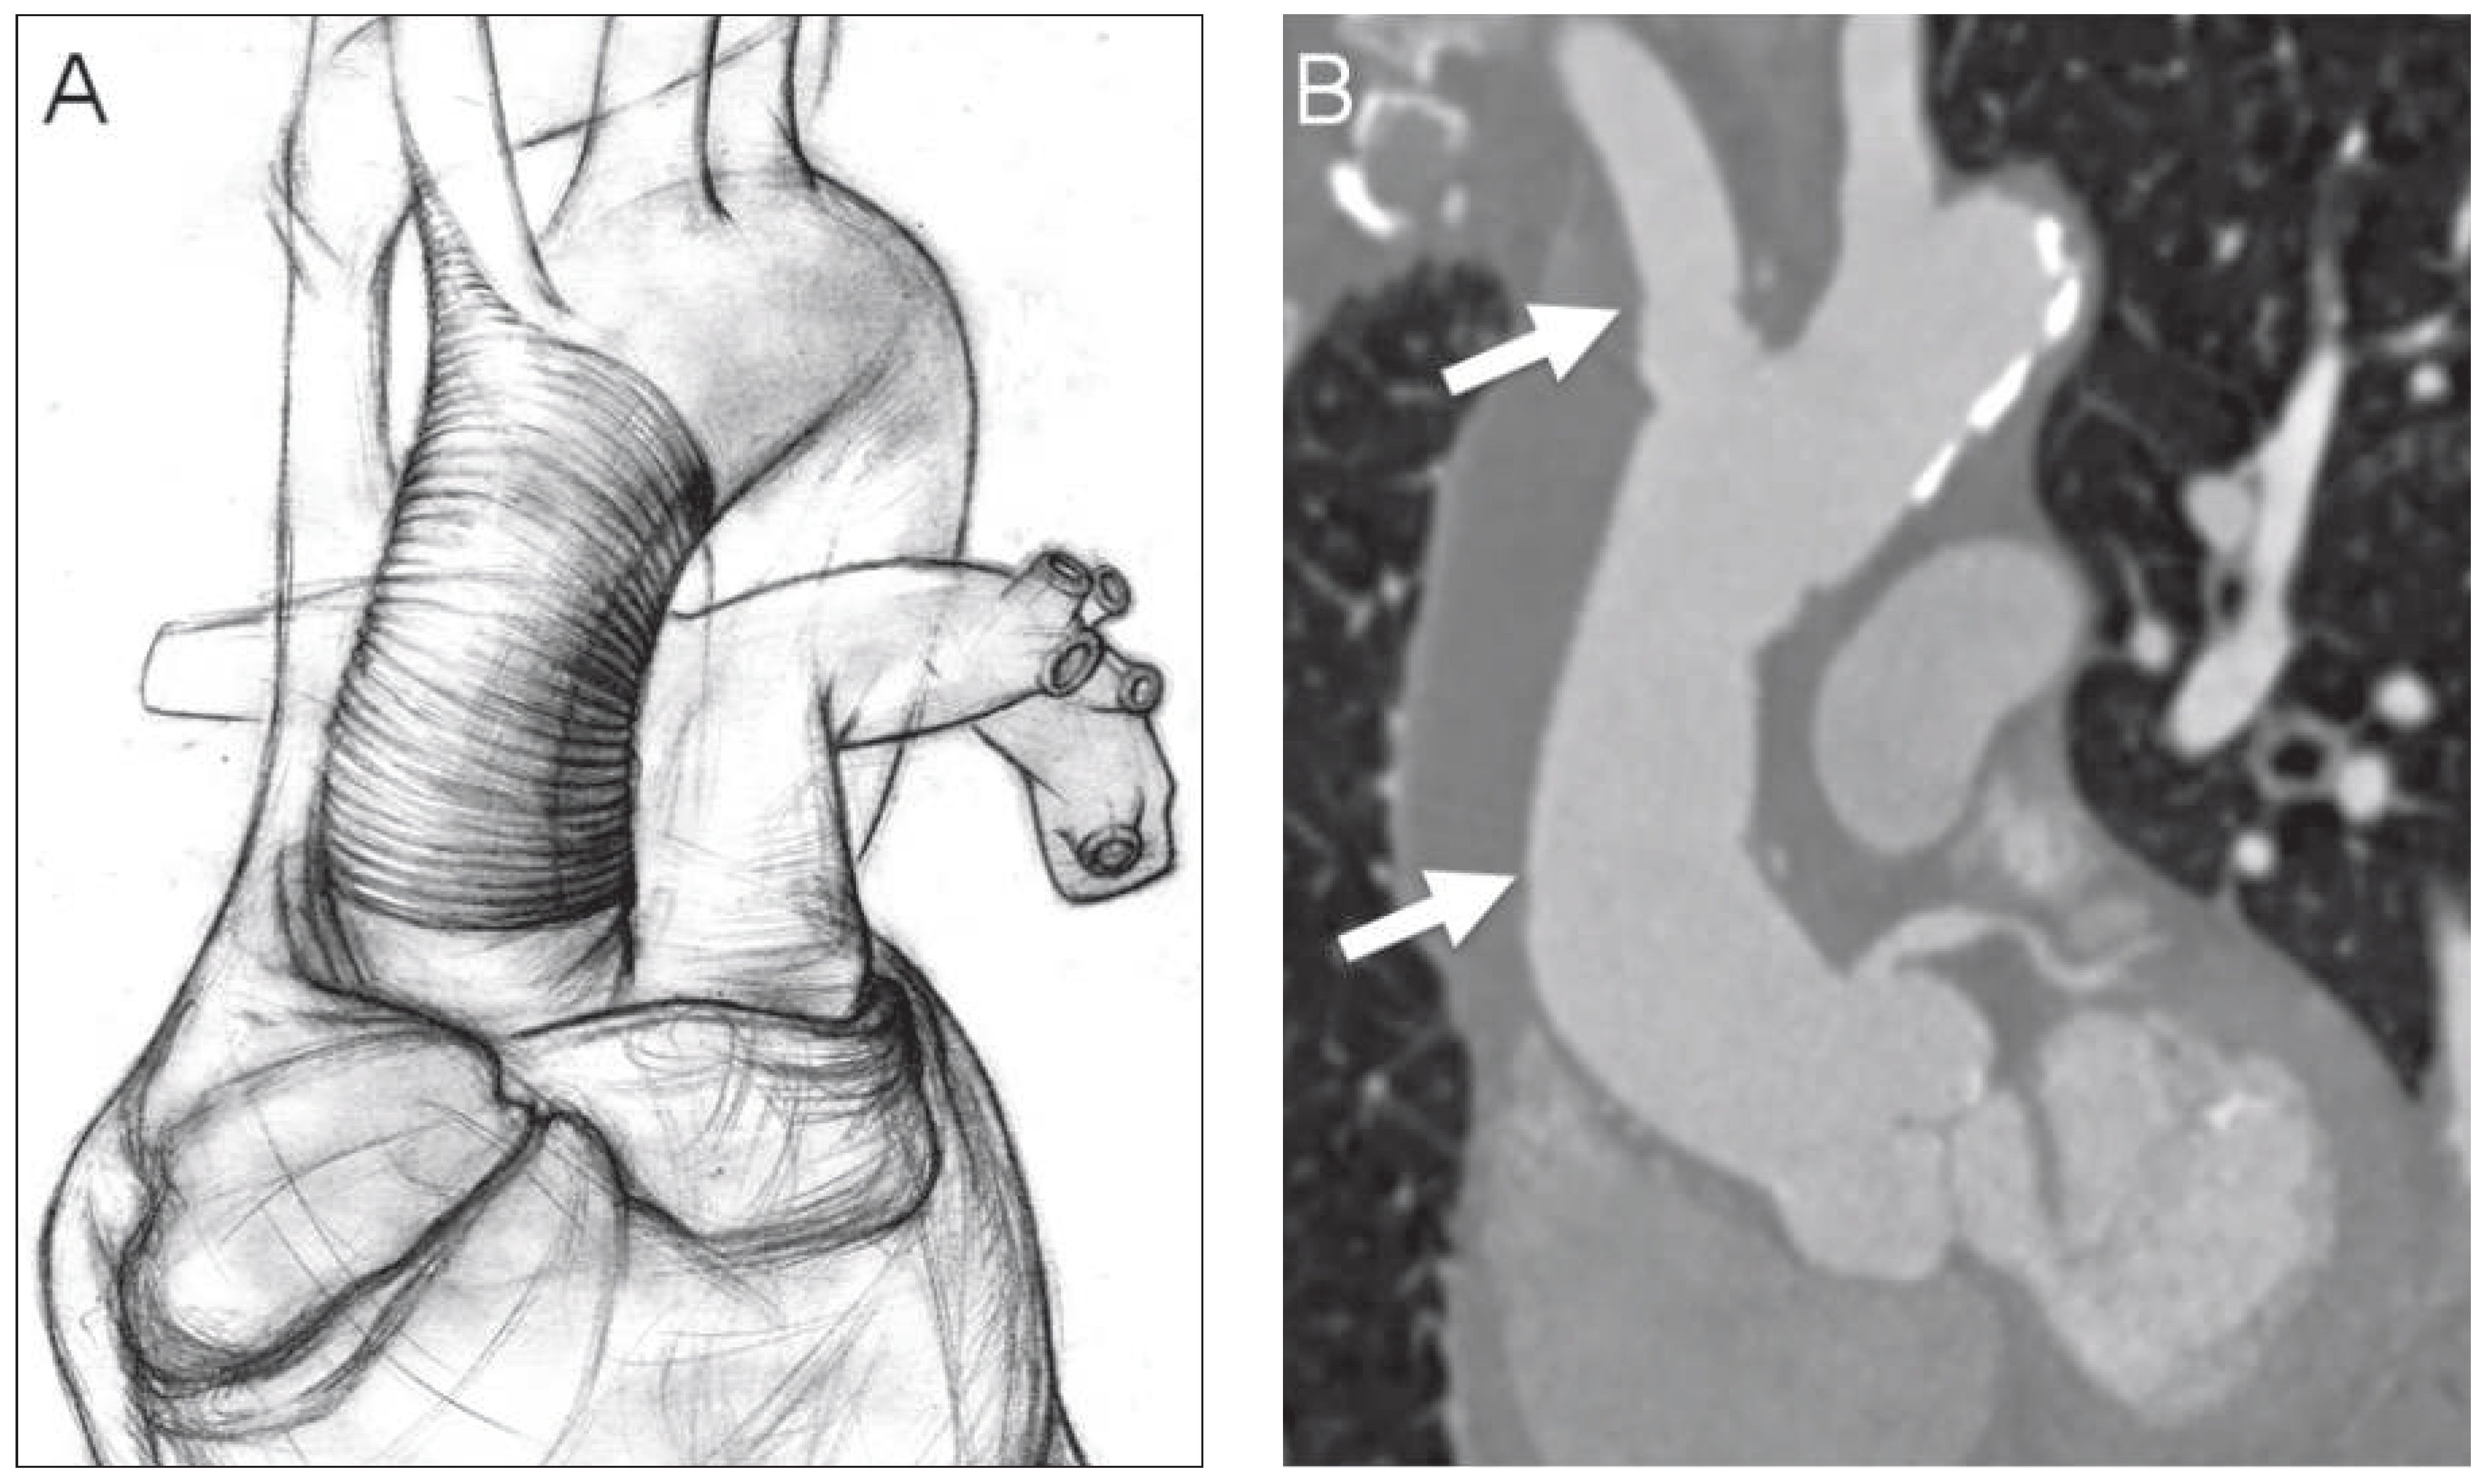

Urgent surgery was performed using a cardiopulmonary bypass via arterial and venous femoral cannulation, the patient was cooled down to 28 °C (82 °F) bladder temperature and the sternum was opened. Aher deep hypothermic circulatory arrest was installed, the aorta was opened and antegrade cerebral perfusion catheters were introduced. We found a ruptured plaque at the base of the brachiocephalic trunk which subsequently had led to aortic rupture. The thickened wall of the false aneurysm including the base of the brachiocephalic trunk and the proximal part of the aortic arch were resected. An appropriately trimmed Gelweave™ grah (26 × 8 mm, Vascutek, UK) was anastomosed with an end-to-end technique (Figure 2A) and no additional grah was needed for replacement of the proximal brachiocephalic trunk. Aher de-airing, cardiopulmonary bypass was reinstalled via the Gelweave™ grah. During re-warming the prosthesis was anastomosed to the proximal part of the ascending aorta combined with a single venous bypass grah to the right coronary artery due to a relevant proximal stenosis shown in the pre-operative angiogram.

Figure 2. A: Illustration of the repair technique showing the single Gelweave™ graft with two end-to-end anastomoses. B: Postoperative CT scan. White arrows mark the proximal and distal anastomosis of the prosthesis.

A postoperative CT scan (Figure 2B) revealed a good result. The early postoperative course was uneventful, however severe pre-existing obstructive pulmonary disease led to a delayed recovery of the patient.